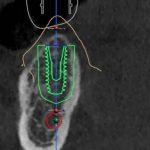

طراحی دیجیتال:

با استفاده از نرمافزارهای پیشرفته، محل قرارگیری دقیق ایمپلنت طراحی و شبیه سازی میشود

ساخت راهنمای جراحی( Guide surgical):

با پرینتر سه بعدی ابزار خاصی تولید میشود که به جراح کمک میکند ایمپلنت را با دقت بسیار بالا در جایگاه مناسب قرار دهد

دقت بالا: موقعیت دقیق ایمپلنت از پیش تعیین میشود و خطر آسیب به بافتها عصبها کاهش مییابد